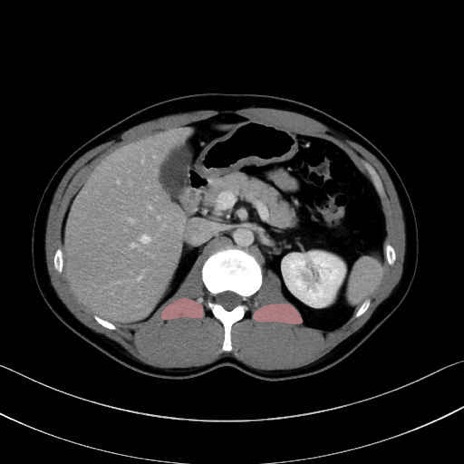

腰方形筋 (Quadratus lumborum)